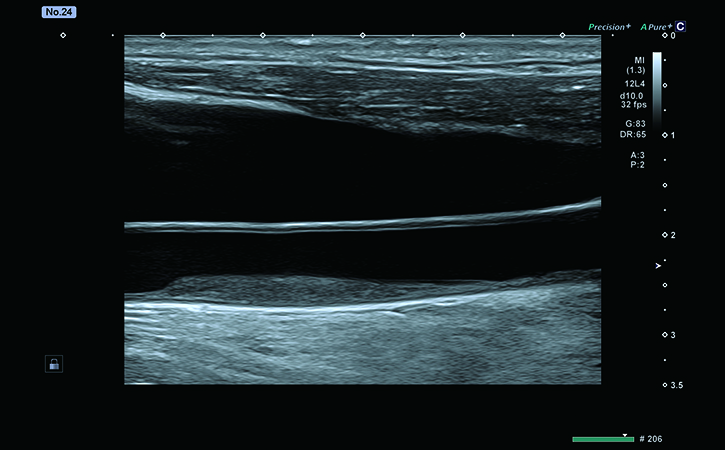

頸動脈エコー

- 動脈硬化の程度

- 脳梗塞や心疾患のリスク評価